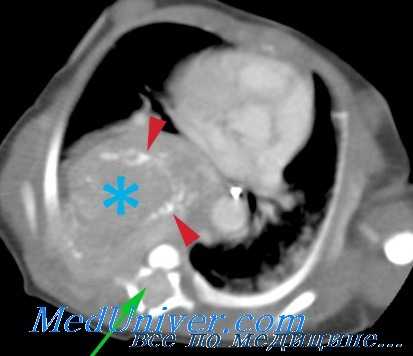

Компьютерная томография более детально дает информацию об анатомическом отношении опухоли к окружающим тканям и органам, позволяет оценить структуру опухоли (рис. 5).

Рис. 5. КТ нейрогенного образования забрюшинного пространства справа